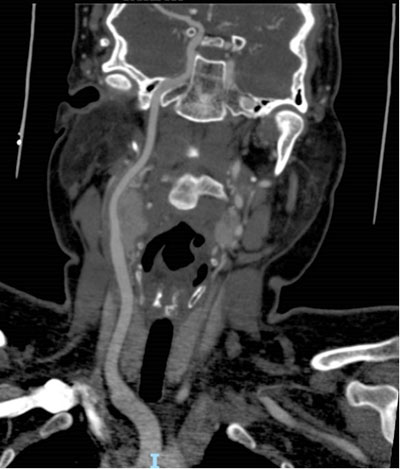

血管外科近期收治一37岁女性患者,发现右颈部肿物1年余,我院颈部CTA检查提示:右颈动脉体瘤,大小约4×3×3cm,瘤体完全包裹颈内、颈外动脉。

术前CTA

该患者属于Shambin分型 Ⅲ型,术前头颈部CTA可见瘤体已完全包裹患侧颈内、颈外动脉,评估肿瘤侵犯颈内动脉可能性大,需行血管重建,而大隐静脉的长期通畅性最好。术前,血管外科王劲松团队进行了周密的评估和设计,先行颈动脉体瘤供瘤血管介入栓塞术,减少术中出血风险。24小时后再行颈动脉体瘤切除。术中探查证实肿瘤完全包裹颈内、外动脉,无法将颈内动脉从肿瘤中分出。手术团队分3步实施手术:先行血管转流,临时保障颈内动脉血流;然后完整切除颈动脉体瘤及包裹的血管;再取患者自体大隐静脉重建颈内动脉。